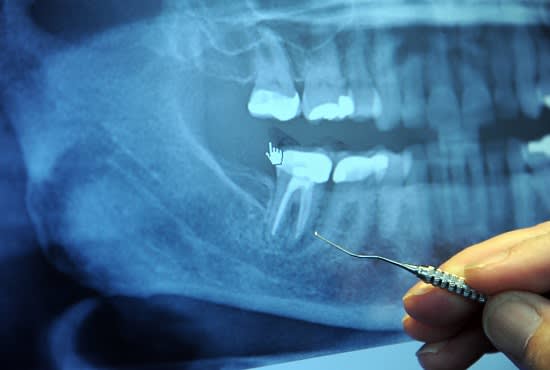

I am a professional dentist, working in this field for many years. I can give the best opinion and diagnosis based on symptoms and x rays. I will give treatment plan and give the second opinion so you don't get scammed by quakes or the dentists who overdo the treatments.I will tell you the remedies in case of an emergency when there is no dentist in your area